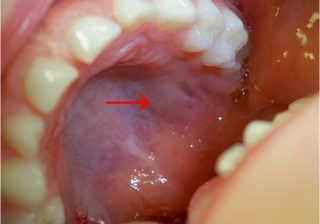

Breast Self Examination – It Can Save Your Life